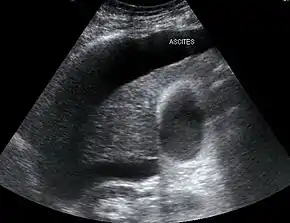

| Liver histology is altered in HRS while kidney histology is normal. The upper image is a trichrome stain (chicken wire appearance) of cirrhosis of the liver, the most common cause of HRS. | |

Both types of hepatorenal syndrome share three major components: altered liver function, abnormalities in circulation, and kidney failure. As these phenomena may not necessarily produce symptoms until late in their course, individuals with hepatorenal syndrome are typically diagnosed with the condition on the basis of altered laboratory tests. Most people who develop HRS have cirrhosis, and may have signs and symptoms of the same, which can include jaundice, altered mental status, evidence of decreased nutrition, and the presence of ascites.[2] Specifically, the production of ascites that is resistant to the use of diuretic medications is characteristic of type 2 HRS. Oliguria, which is a decrease in urine volume, may occur as a consequence of kidney failure; however, some individuals with HRS continue to produce a normal amount of urine.[3] As these signs and symptoms may not necessarily occur in HRS, they are not included in the major and minor criteria for making a diagnosis of this condition; instead HRS is diagnosed in an individual at risk for the condition on the basis of the results of laboratory tests, and the exclusion of other causes.[3]

The major criteria include liver disease with portal hypertension; kidney failure; the absence of shock, infection, recent treatment with medications that affect the function of the kidney (nephrotoxins), and fluid losses; the absence of sustained improvement in kidney function despite treatment with 1.5 litres of intravenous normal saline; the absence of proteinuria (protein in the urine); and, the absence of kidney disease or obstruction of kidney outflow as seen on ultrasound.[3]